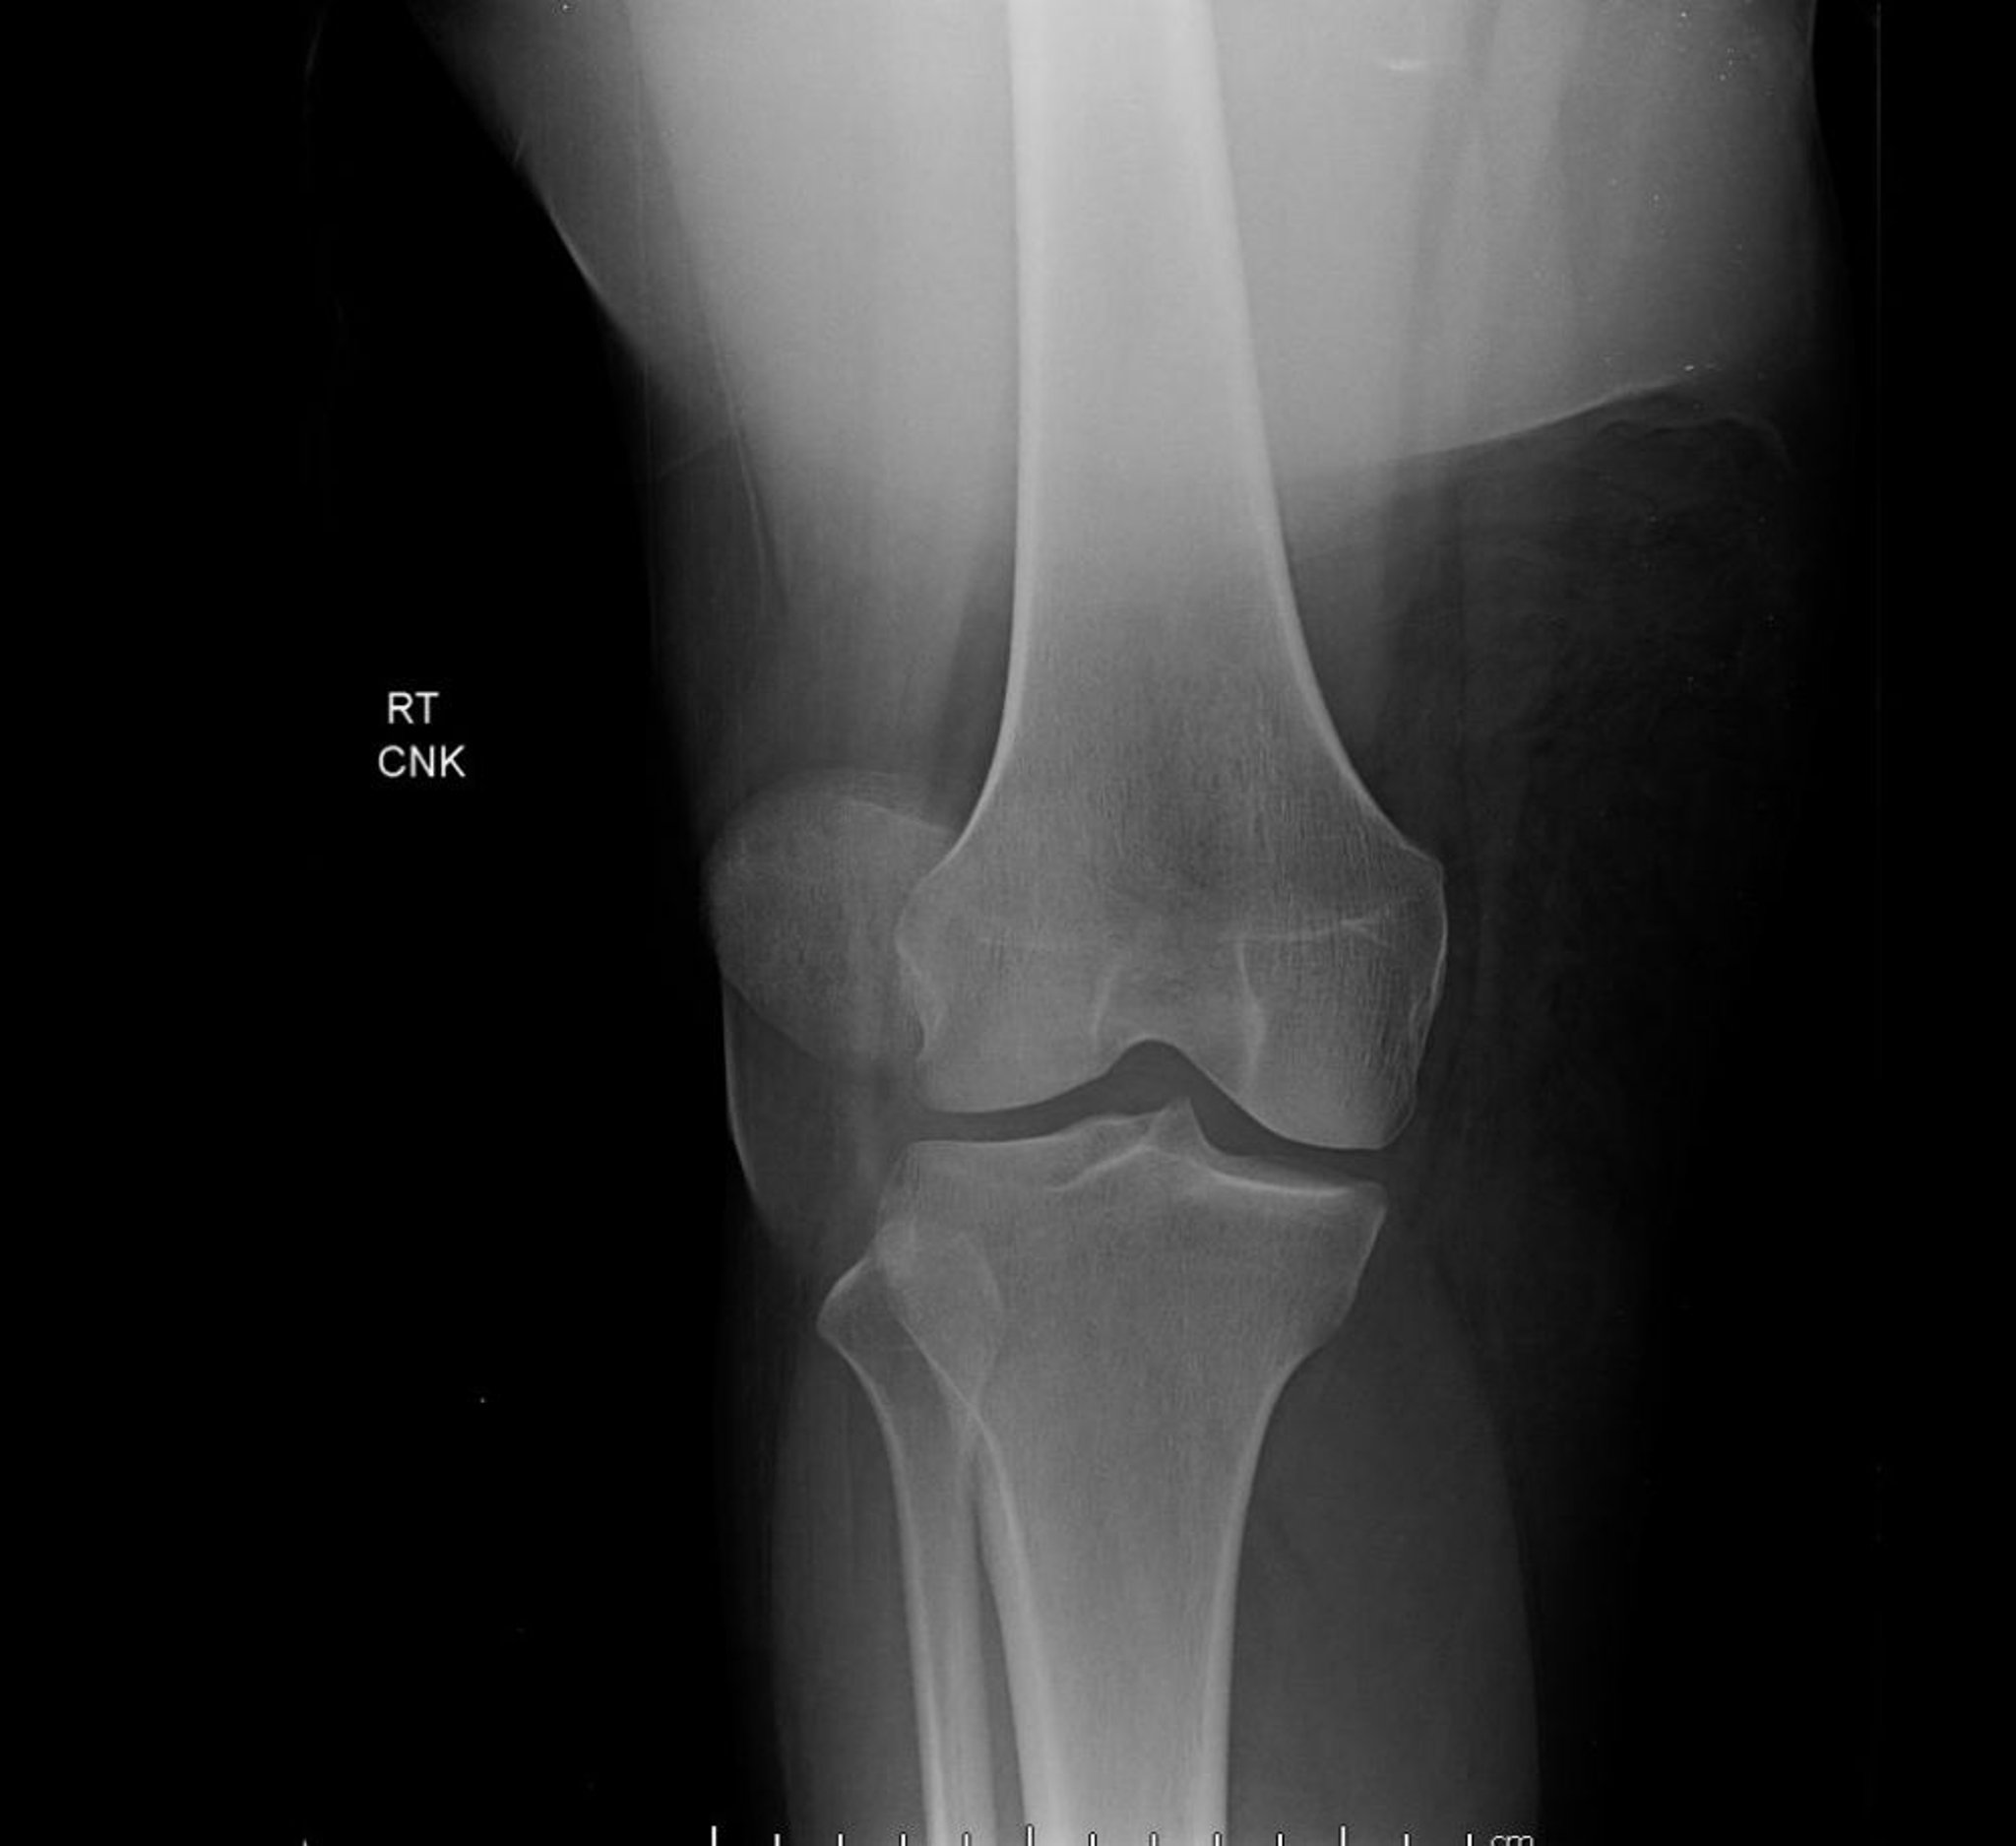

Вывих надколенника (рентгеновское исследование)

На данной переднезадней проекции колена показан вывих надколенника, характеризующийся крайним боковым смещением надколенника наружу от его нормального положения между мыщелками бедренной кости.

Image courtesy of Danielle Campagne, MD.